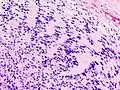

Illustrations

Neurinome subcutané_Antoni_B.jpg)

_Antoni_B.jpg)

_S-100_immunostain.jpg)